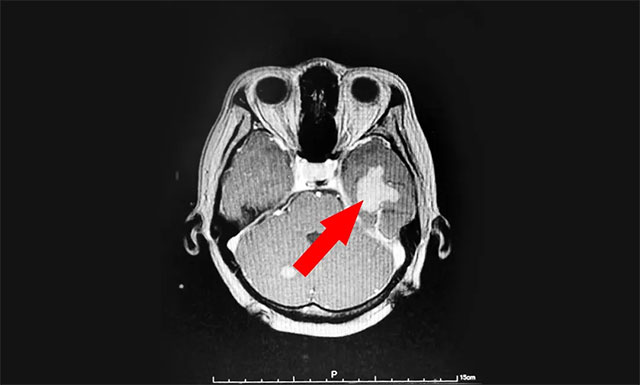

今年43歲的患者湯女士(化名),于2020年8月因頭暈伴體倦乏力至當(dāng)?shù)蒯t(yī)院就診,查體PET-CT:右肺上葉前段結(jié)節(jié),考慮周圍型肺癌。右肺門、縱膈多發(fā)淋巴結(jié)轉(zhuǎn)移,顱內(nèi)多發(fā)轉(zhuǎn)移。湯女士在外院接受放射治療后,頭暈乏力等癥狀得到了一定的改善。

▲ 來藍(lán)十字治療前患者的囊性轉(zhuǎn)移瘤病灶